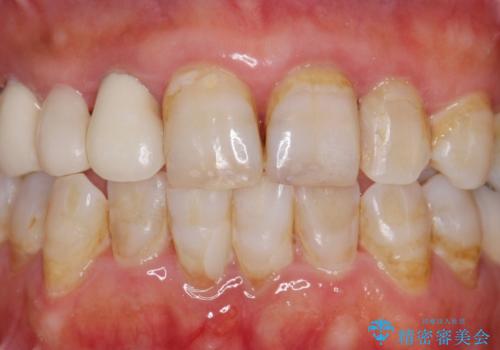

- 被せ物がかけてしまったことを主訴に来院された患者様です。

口腔内を精査したところ、右上のブリッジの内側(口蓋側)がかけており、下の前歯(右下1)には唇舌側に瘻孔を伴う大きな根尖病変ができていました。

右上のブリッジ(右上④3②)のやりかえと、下の前歯(右下1)の根管治療を行った後セラミッククラウンによる補綴治療を行いました。

とにかく早く終わらせたいとのご希望により、1回の治療時間を長くおとりして治療期間の短縮に努めました。

(初診を含め、治療期間:2ヶ月、来院回数:7回)

ブリッジとクラウンの自然な仕上がりと咬み心地に喜んで下さいました。

精密な根管治療により、下の前歯の歯ぐきにできていた瘻孔もなくなりました。

短期間(2ヶ月)でしっかりとした治療が受けられたとご満足頂けました。